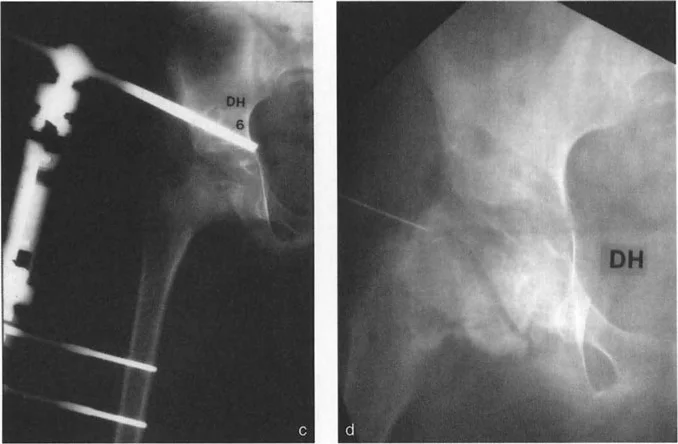

- انزلاق مشاش رأس الفخذ (SCFE): حالة شائعة تحدث غالبًا في مرحلة المراهقة، حيث ينزلق رأس عظم الفخذ عن عنقه عند صفيحة النمو.

* علامة دريمان (Drehmann sign): وهي علامة مميزة لانزلاق مشاش رأس الفخذ (SCFE)، حيث يحدث دوران خارجي إجباري للطرف عند ثني الورك بشكل سلبي.

- صور الأشعة الجانبية عبر الطاولة (Cross-table lateral view): تُعد هذه الصورة حاسمة لتقييم الزاوية الأمامية لعنق الفخذ (ANSA) وتحديد التشوهات في المستوى السهمي. يُشدد الأستاذ الدكتور محمد هطيف على ضرورة الحصول على هذه الصورة بشكل صحيح، بحيث تكون موجهة بالنسبة لـ "المنظر الأمامي الحقيقي للورك" وليس الركبة، لتجنب ما يُسمى "فخ الالتواء".

فخ الالتواء (The Torsional Trap): إذا كان هناك تشوه التوائي شديد في عظم الفخذ (مثل زيادة في الميل الأمامي لعنق الفخذ)، فإن المنظر الأمامي الحقيقي للركبة (الرضفة متجهة للأمام) سيكون مختلفًا تمامًا عن المنظر الأمامي الحقيقي للورك. إذا قام فني الأشعة بالحصول على الصورة الجانبية عبر الطاولة بشكل عمودي على المنظر الأمامي الحقيقي للركبة بدلاً من الورك، فقد تظهر الزاوية الأمامية لعنق الفخذ وكأنها مُنثنية بشكل ملحوظ في الفيلم. هذا يخلق تشوه انثناء ثابت ظاهري للورك، وهو في الواقع خطأ ناتج عن الدوران وليس تشوهًا سهميًا حقيقيًا.

القاعدة التشخيصية: لا يتم تأكيد وجود تشوه انثناء ثابت حقيقي ناتج عن انحناء هيكلي في عنق الفخذ إلا إذا ظهرت الزاوية الأمامية لعنق الفخذ مُنثنية بشكل ملحوظ، وتطابقت الصورة الجانبية عبر الطاولة للورك تمامًا مع المنظر الجانبي الحقيقي للركبة.